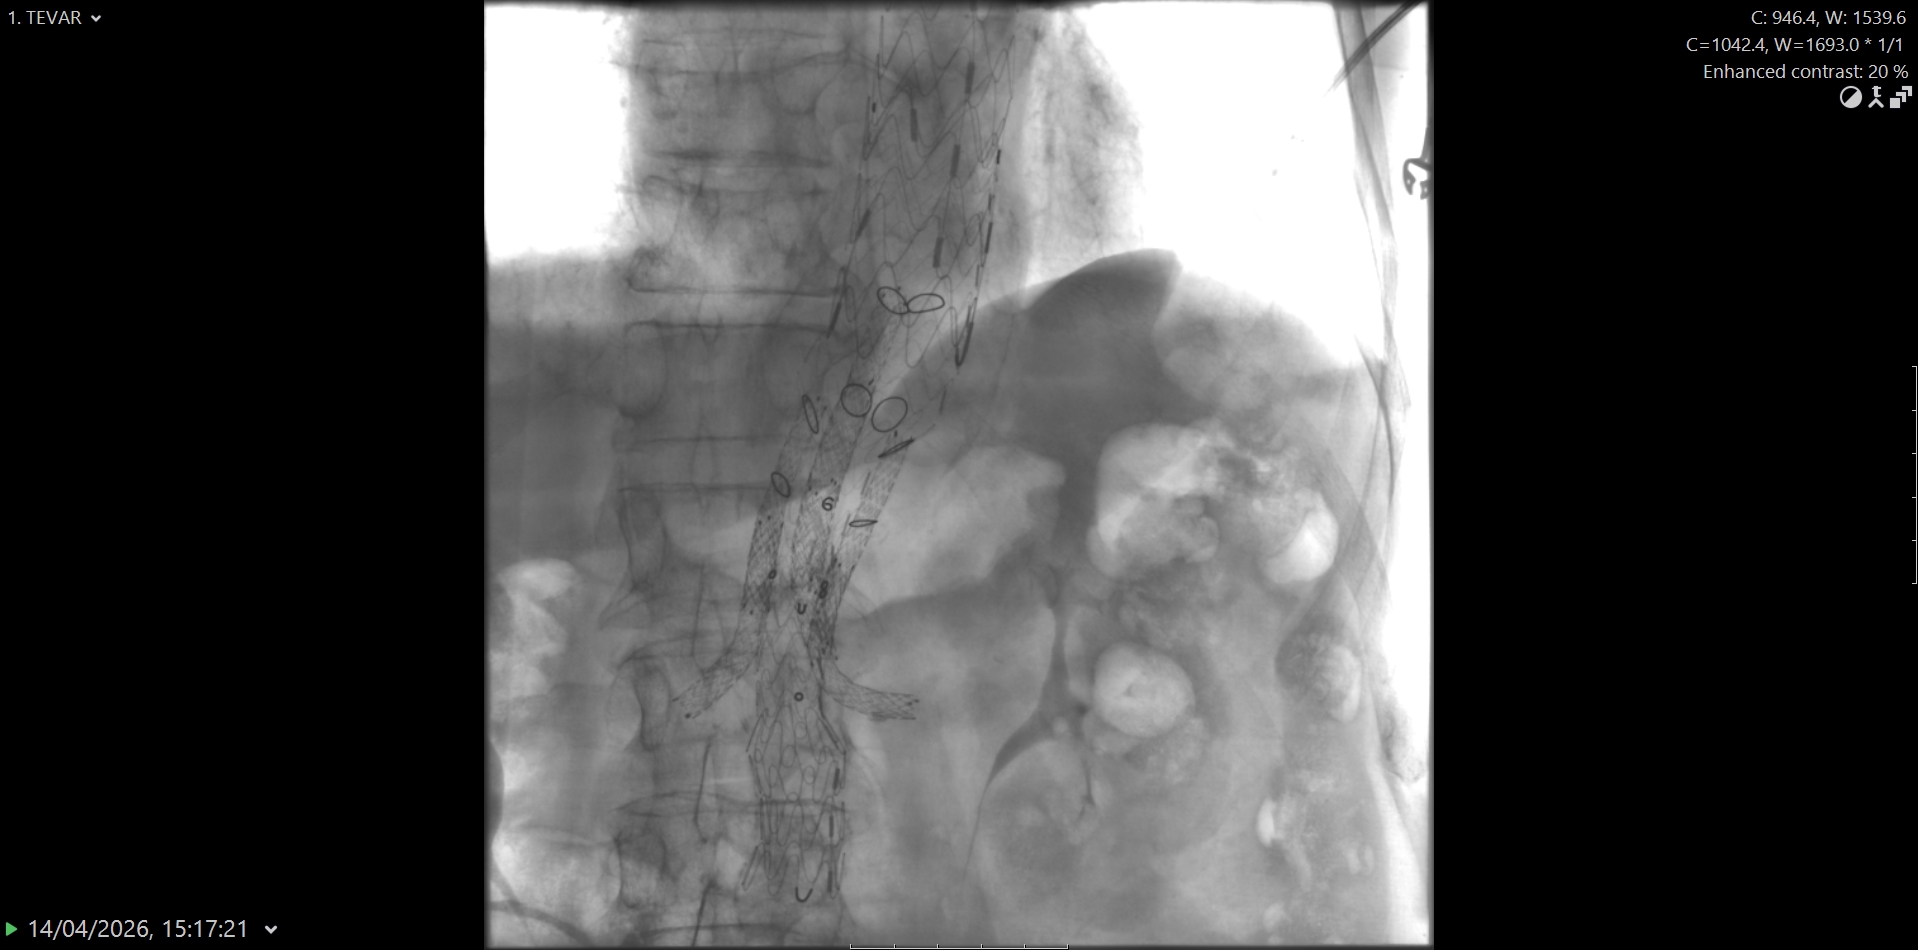

Riječ je o proceduri poznatoj kao BEVAR (branched endovascular aortic repair) koja je primijenjena kod pacijenta s istodobnom aneurizmom i disekcijom torakalne aorte, životno ugrožavajućim stanjima koja zahtijevaju visoko specijaliziran pristup i vrhunsku medicinsku opremu.

„Ovakvi zahvati predstavljaju vrhunac suvremene endovaskularne medicine i zahtijevaju iznimnu koordinaciju multidisciplinarnog tima koji uključuje interventne radiologe, kardiokirurge, vaskularne kirurge, anesteziologe, inženjere radiologije, instrumentarke i anestezičare. Tijekom zahvata ugrađena su ukupno tri stenta duž aorte, od arterije subklavije do bifurkacije aorte. Kako bi se osigurala adekvatna prokrvljenost vitalnih organa, postavljen je posebno dizajniran stent s otvorima za bubrežne arterije te arterije koje opskrbljuju crijeva“, pojasnio je dr. Gojko Bogdan, voditelj Kliničkog odjela za vaskularnu i intervencijsku radiologiju te dodao se pacijent nakon zahvata osjeća odlično.